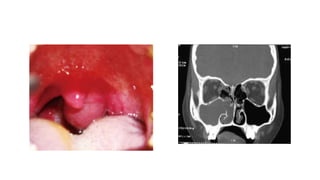

Antrochoanal polyp

• Antrochoanal polyps are the most common type of choanal polyp.

• Other sites of origin may be sphenoid, ethmoid, rarely septum, and

inferior turbinate.

• Antrochoanal polyps represent 4–6% of all polyps, and in the pediatric

population, up to 33%.

• They have an antral and choanal component. These typically arise

from the posterior wall of maxillary antrum and often have a thin

“neck” that passes through the maxillary sinus ostium (or accessory ostium).

• They are often unilateral, but may be bilateral on rare occasions.

• Macroscopically, these range from erythematous to cystic with the latter

often seen in the antral portion.

• Microscopically, these polyps are lined by ciliated pseudostratified

epithelium that is usually intact, with a thin basement membrane.

• Stroma may exhibit myxoid change and stromal giant cells, but usually

lacks a significant inflammatory component.

• Rarely, degenerative changes including cholesterol granulomas and

angiomatous change may be found.

• In antronasal polyps sometimes, the polyp will be narrowed as it passes through the

maxillary os, resulting in a dumbbell configuration on coronal CT. The medial wall of

the maxillary sinus is usually bowed into the nasal cavity. (Fig 1)

• In antrochoanal polyp the most helpful radiologic feature is the

mass itself extending into the nasopharynx. (Fig 2)